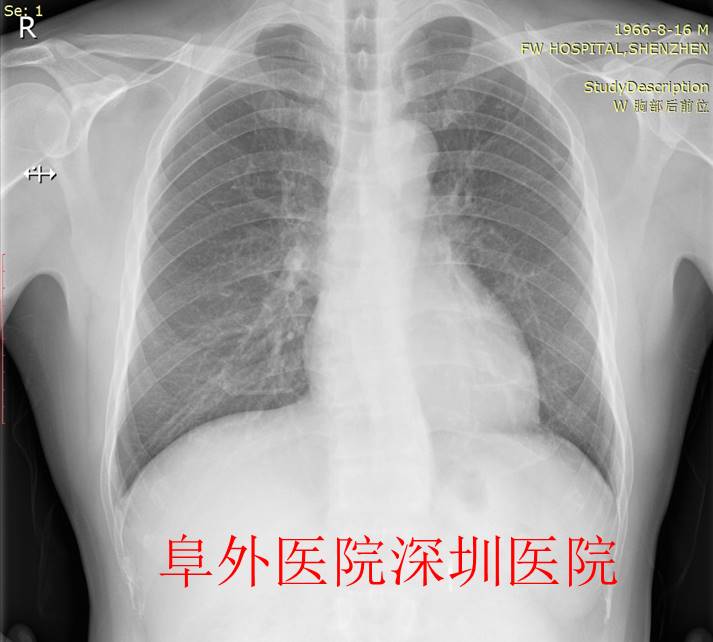

最终,患者及家属经过充分考虑后决定尝试房颤射频消融治疗,我们团队首先给患者充分的术前药物治疗,改善患者心功能。经过周密的术前准备后,患者顺利接受了房颤射频消融治疗并成功恢复窦性心律。术后恢复超好。术后满一年随访,巨大的心脏一切恢复了正常,完全不需要药物治疗,手术效果太神奇了。希望更多的类似患者收益,不再受病痛困扰,尤其是房颤心衰患者。神奇的导管射频消融术,房颤合并心衰患者重获新生,避免心脏移植及外科手术,或者心脏起搏器等治疗。

图8. 术后1年胸片提示心影大小完全恢复正常